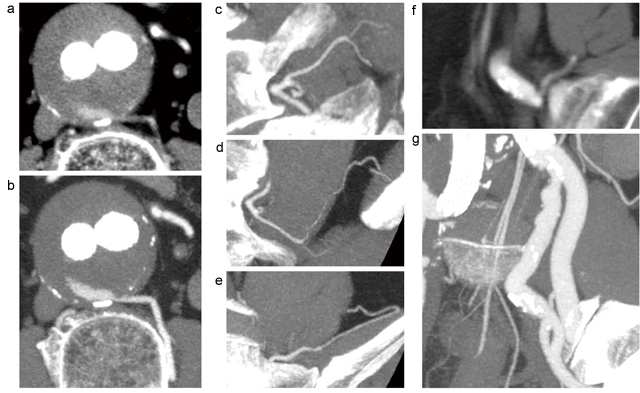

まず,ダブルオブリーク機能を用いて大動脈瘤から責任動脈を逆行性にたどっていき(図3),超選択的CTA作成のための下調べを行った。また,その作成過程で,分岐の形態,径,屈曲程度などを把握しつつ,カテーテル挿入が可能か,どの器具をどういう手順で使うか,そのほか術中の透視角度などについてシミュレーションを行った。

図3 ダブルオブリーク機能を用いて作成血管を下調べ

a:エンドリーク部の平均表示 b:エンドリーク部のMIP表示

c:L4椎体左あたりのMIP表示 d:左大腰筋あたりのMIP表示 e:左腸骨窩あたりのMIP表示

f:左仙腸関節あたりの平均表示 g:左内腸骨動脈本幹のMIP表示